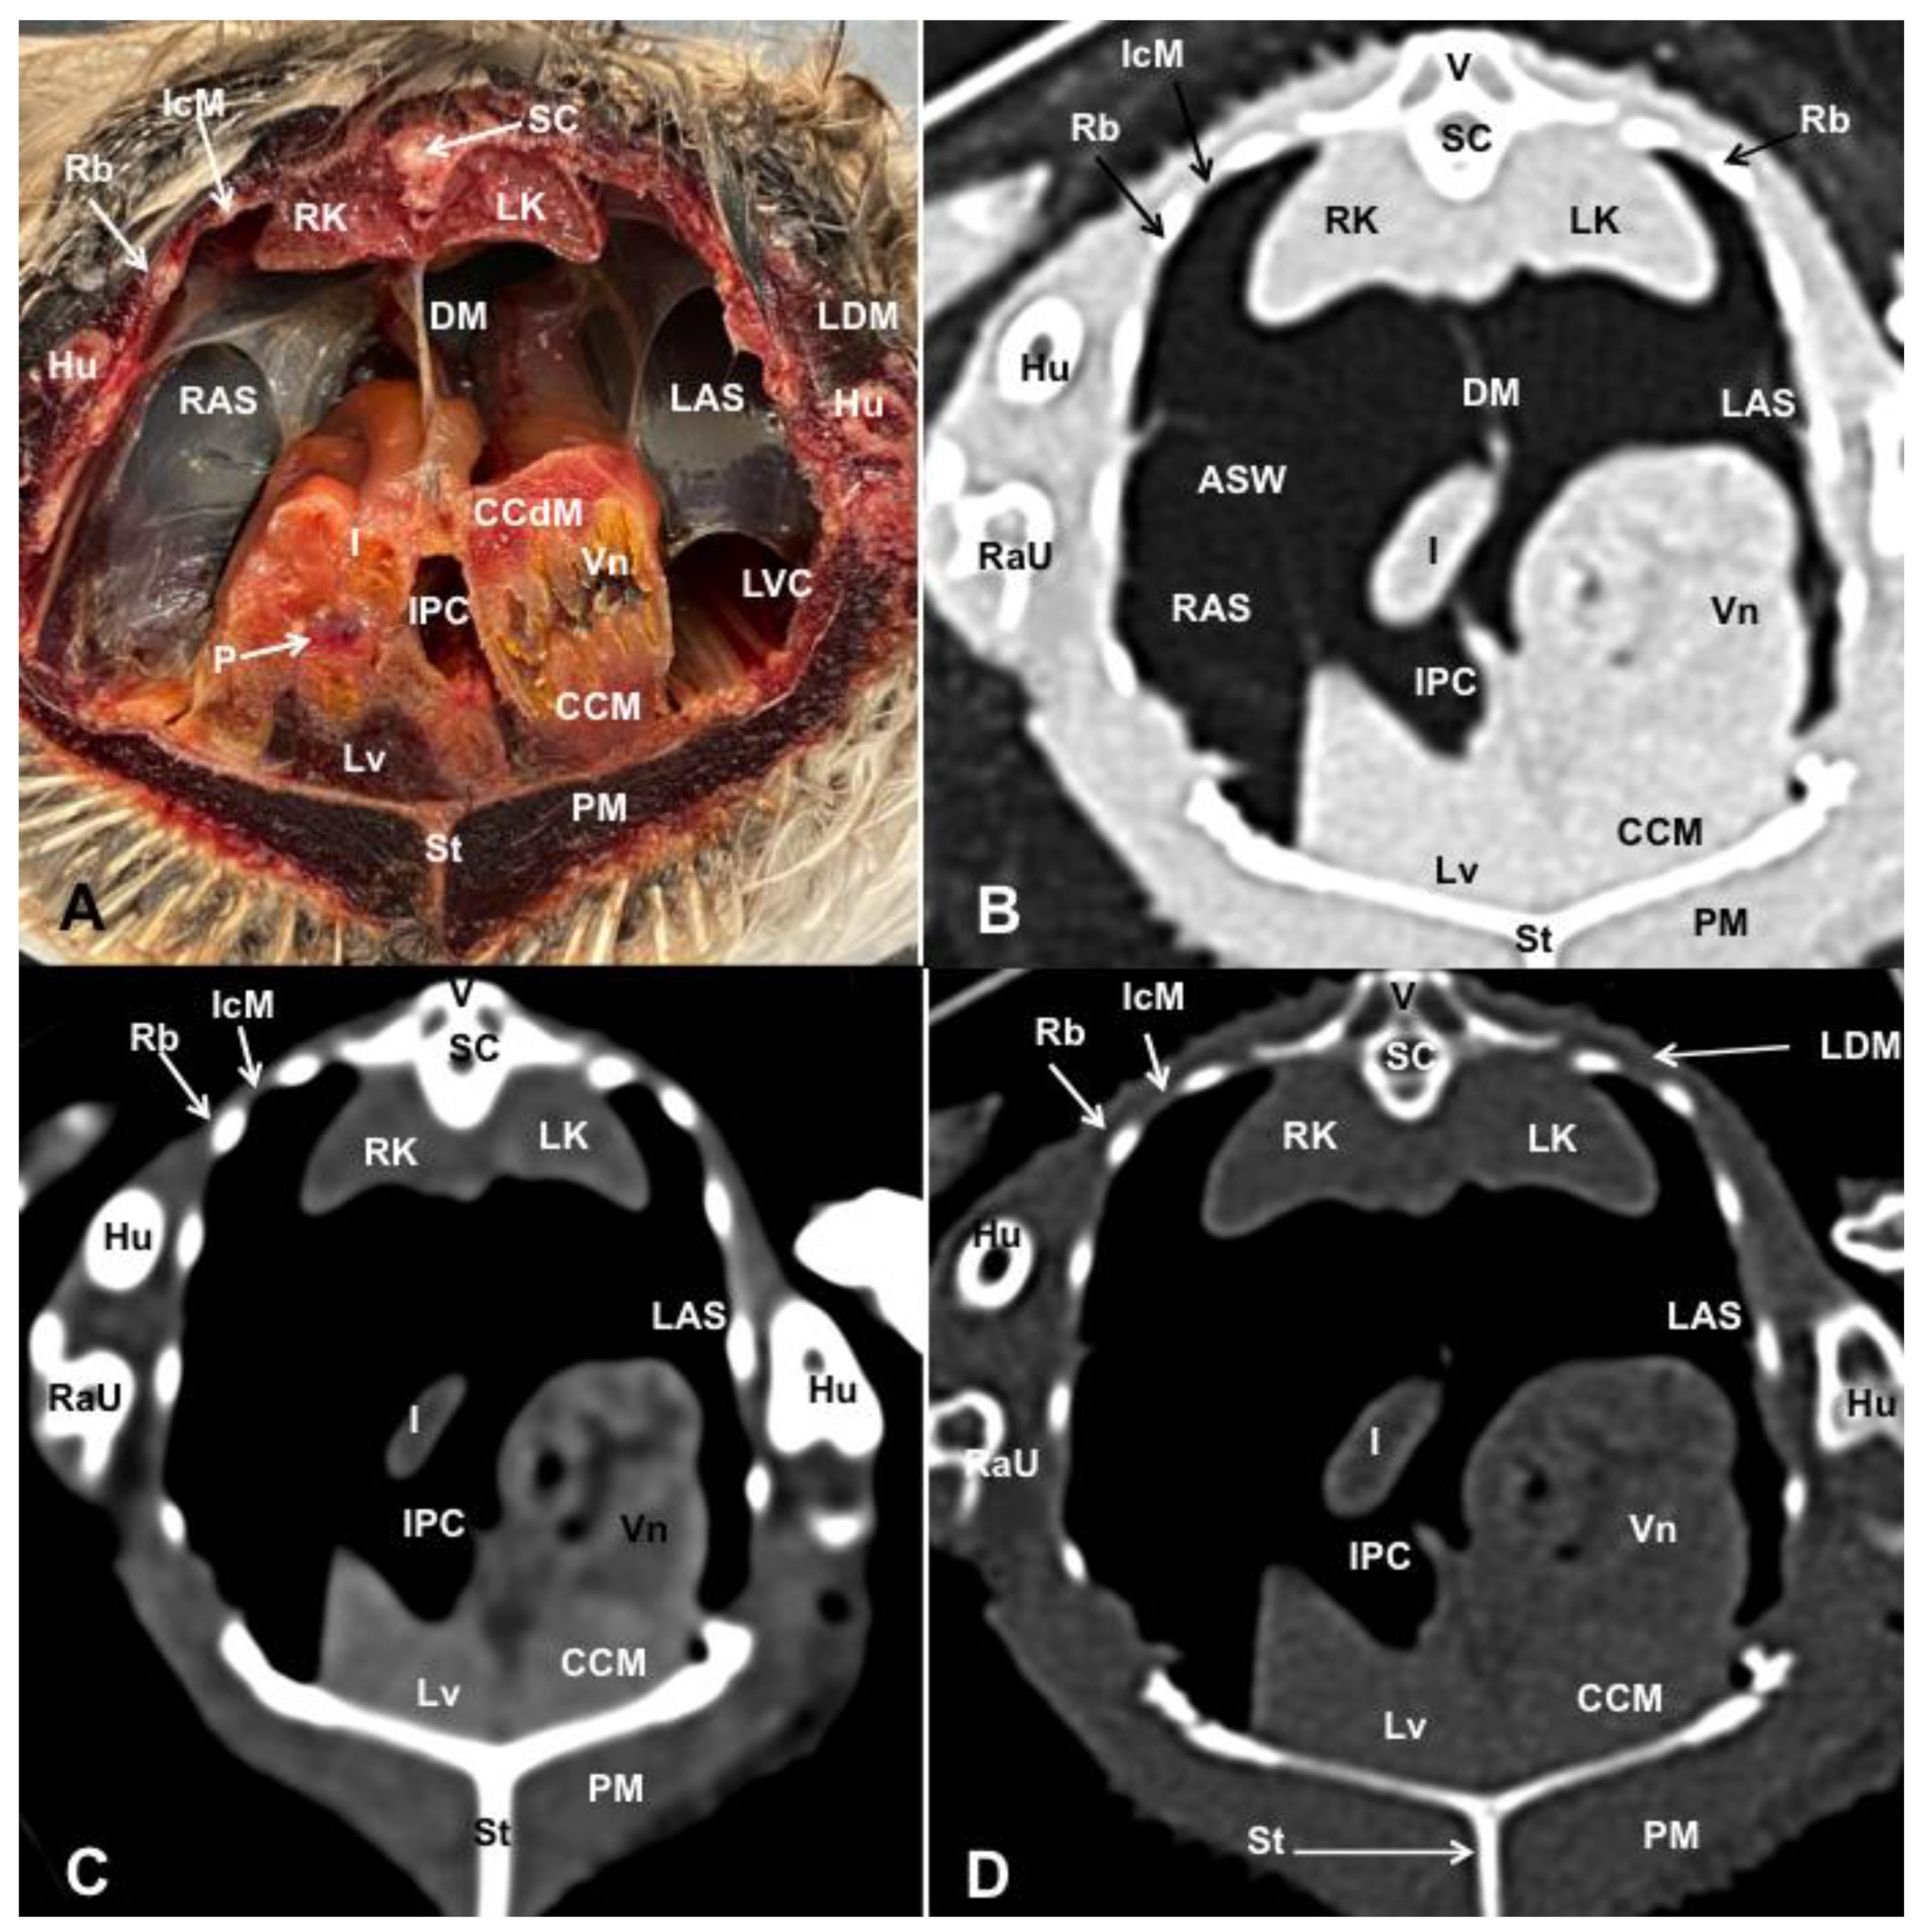

3.1. Anatomical Dissections and Cross-Sections

3.2. Computed Tomography Images